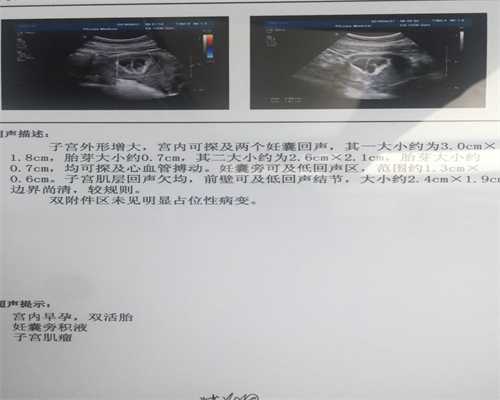

有人提出试管婴儿可能会流产或胚胎停止可能高于自然妊娠。如果确诊,应及时考虑怀孕,以避免大量出血和感染。因为每次移植多个胚胎,多胞胎的发病率也很高。多胎妊娠易发生并发症,早产也容易发生。此外,原则上应该执行三元组。然而,10%的堕胎手术机会导致所有胚胎流产。如果患者的输卵管未完全阻塞,移植到子宫腔可能会流入输卵管产生异位妊娠,有时甚至宫内节育合并异位妊娠,应优先考虑,早期诊断和治疗,以免大出血的风险。

试管婴儿的流产率在不同人群中有所不同。例如,对于仅通过输卵管因子的试管婴儿胚胎移植,与正常人群没有差异。从临床角度来看,试管婴儿的人群一般比正常分娩年龄大,而且患者常伴有其他疾病,如子宫内膜异位症,子宫肌瘤等。这些因素也会导致孕妇在怀孕期间出现异常的概率。分娩高于一般人群。